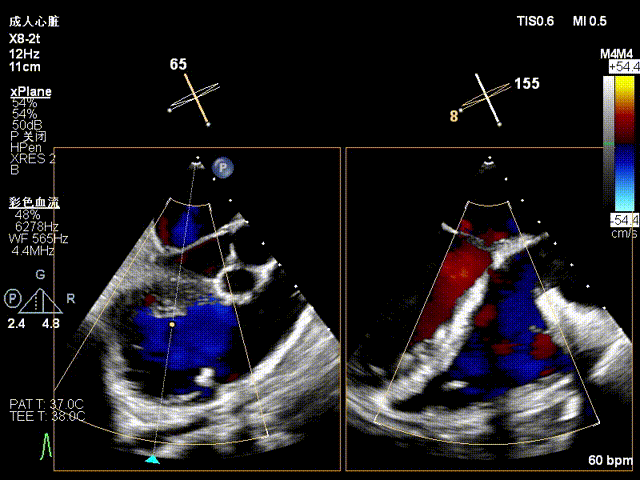

术前超声

术后超声